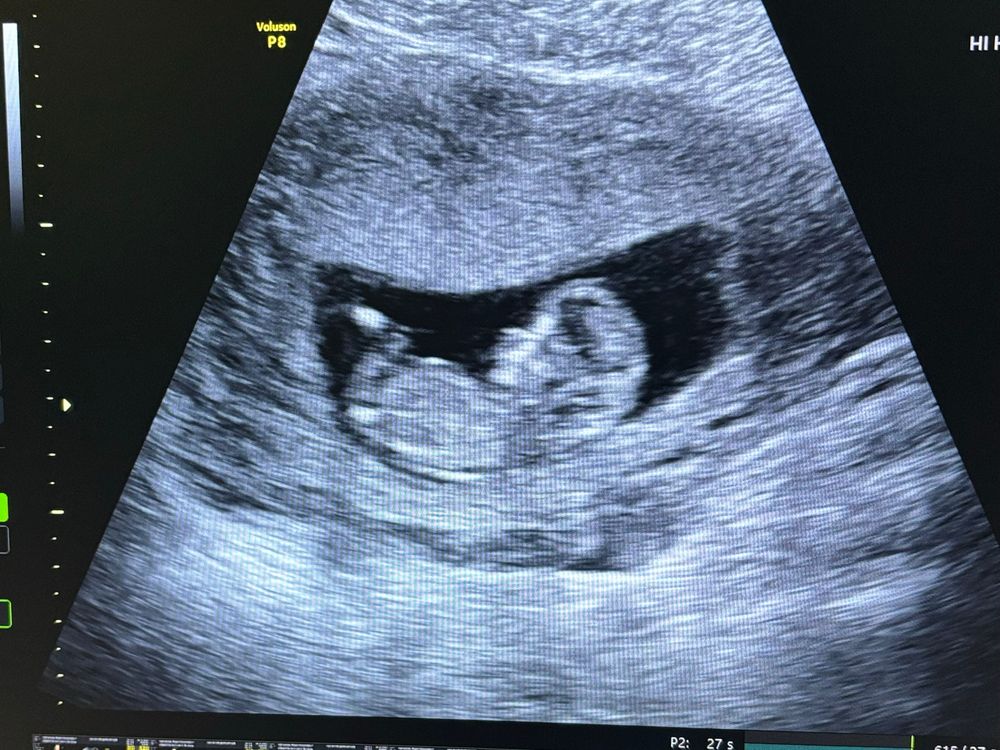

Маша в Клуб беременных год 1 скрининг пройден как думаете кто 😁 Пол малыша Вот и мы прошли первый скрининг, предположили мальчика 😁 , Посмотрите еще 20 записей на эту тему Отменить Ответить Екатерина Там же для пола промежность смотрят, половой бугорок) 06.11.2024 Ответить Маша Екатерина, вот она и сказала что на женские не похоже 😁 тут еще как-то эксперты могут по виду определить 🤣 мне тогда сказали по фотке большинство что профиль женский 😁 и не ошиблись 🤣 06.11.2024 Ответить Пол малыша🍼 Девочки , помогите рассмотреть это мальчик или все таки девочка ?) Чаты Беременных Выберите чат: Январята-2026 Февралята-2026 Мартята-2026 Апрелята-2026 Майчата-2026 Июнята-2026 Июлята-2026 Августята-2026